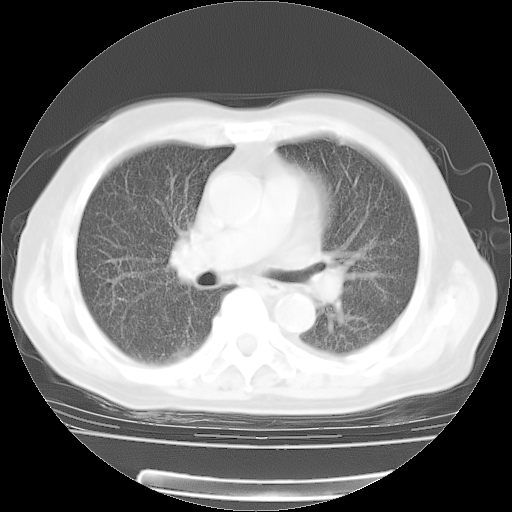

4月28日肺部CT——再次出现类似去年5月9日——透光度降低,“间质性”改变。

4月28日肺部CT——再次出现类似去年5月9日——磨玻璃样、间有“粟粒样”改变。